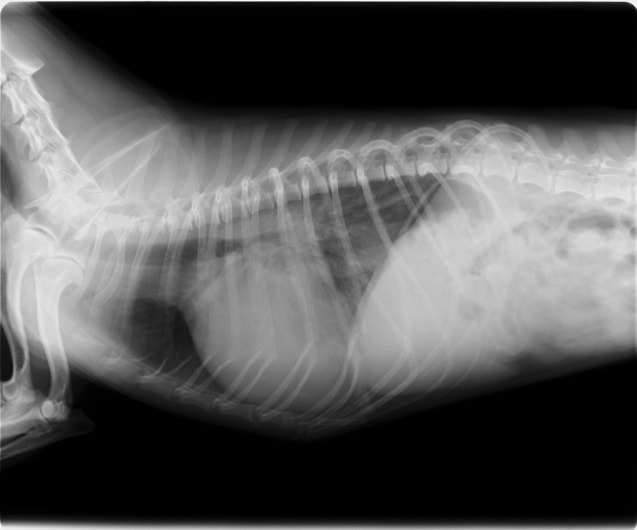

A・B:猫の肥大型心筋症による胸水の貯留 正面像と側面像

C:猫の肥大型心筋症による肺水腫 側面像

D:Cの肺水腫治癒後 側面像

通常、心拡大を認めないことも多く、胸部レントゲン単独での発見は困難ですが、拡張相に移行すると心拡大が認められるようになります。呼吸困難を伴う肥大型心筋症の場合、肺水腫や胸水などの所見が認められることがあります。